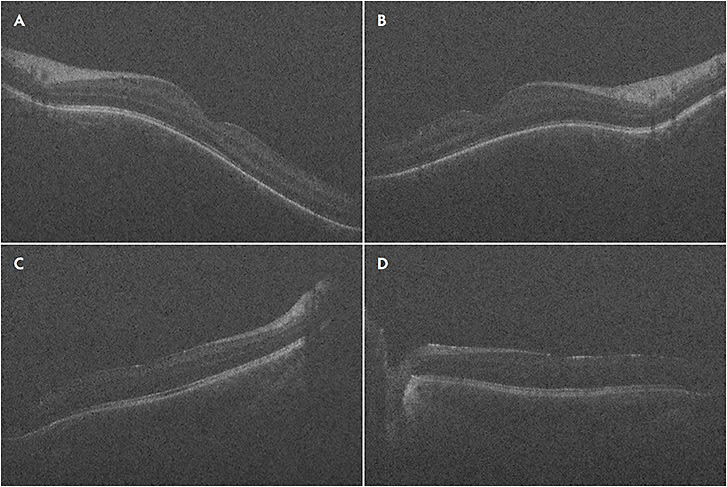

In RD surgery, Mi-iOCT aids in detection of residual subretinal fluid (Figure 4A), small retinal breaks, and proliferative vitreoretinopathy membranes, and it can assist in completion of fluid–air exchange. In TRD surgeries, real-time visualization of the planes may also help achieve more precise delamination and segmentation (Figure 4C).

Intraoperative OCT has proven helpful in cases of fundus-obscuring vitreous hemorrhage (VH). Intraoperatively, after clearing the hemorrhage, iOCT helps elucidate epiretinal membranes, macular edema, hyaloid traction, and retinal detachment.51 Intraoperative OCT can help ensure carefully manipulating and removing a dropped IOL lying on the retina.52 The video available with this article at retinalphysician.com shows a case of using iOCT to safely remove a dropped IOL off the surface of the macula. Similarly, iOCT can aid in visualizing the resting place during vitrectomy for intra-ocular foreign bodies or subluxed native lens (Figure 4B). Lastly, iOCT was found useful for surgeries with a uveitis-related diagnosis; iOCT provided beneficial feedback in 85% of eyes for fluocinolone acetonide placement and 81% of chorioretinal biopsies, while altering surgical decision making in 38% of chorioretinal biopsies.53

Another area that needs refinement is the light scattering and shadowing that surgical instruments cause on iOCT. This limits visualization of the instrument-tissue manipulations as well as the underlying tissues (Figures 4C and 4D). The amount of shadowing varies depending on instrument material, configuration, thickness, and relative orientation to the optical axis of the OCT.60 Development of instruments that minimize scatter and shadowing will allow for more precise tissue manipulation. Ehlers et al reported use of semitransparent rigid plastic material instruments that allowed decreased light scatter and improved visibility of adjacent tissue as well as the tissue immediately underlying the instruments.61 Furthermore, development of new software algorithms may assist in software-based processing of the image to minimize shadowing, as well as localize and track the beam to the area of interest to minimize manual readjustments.